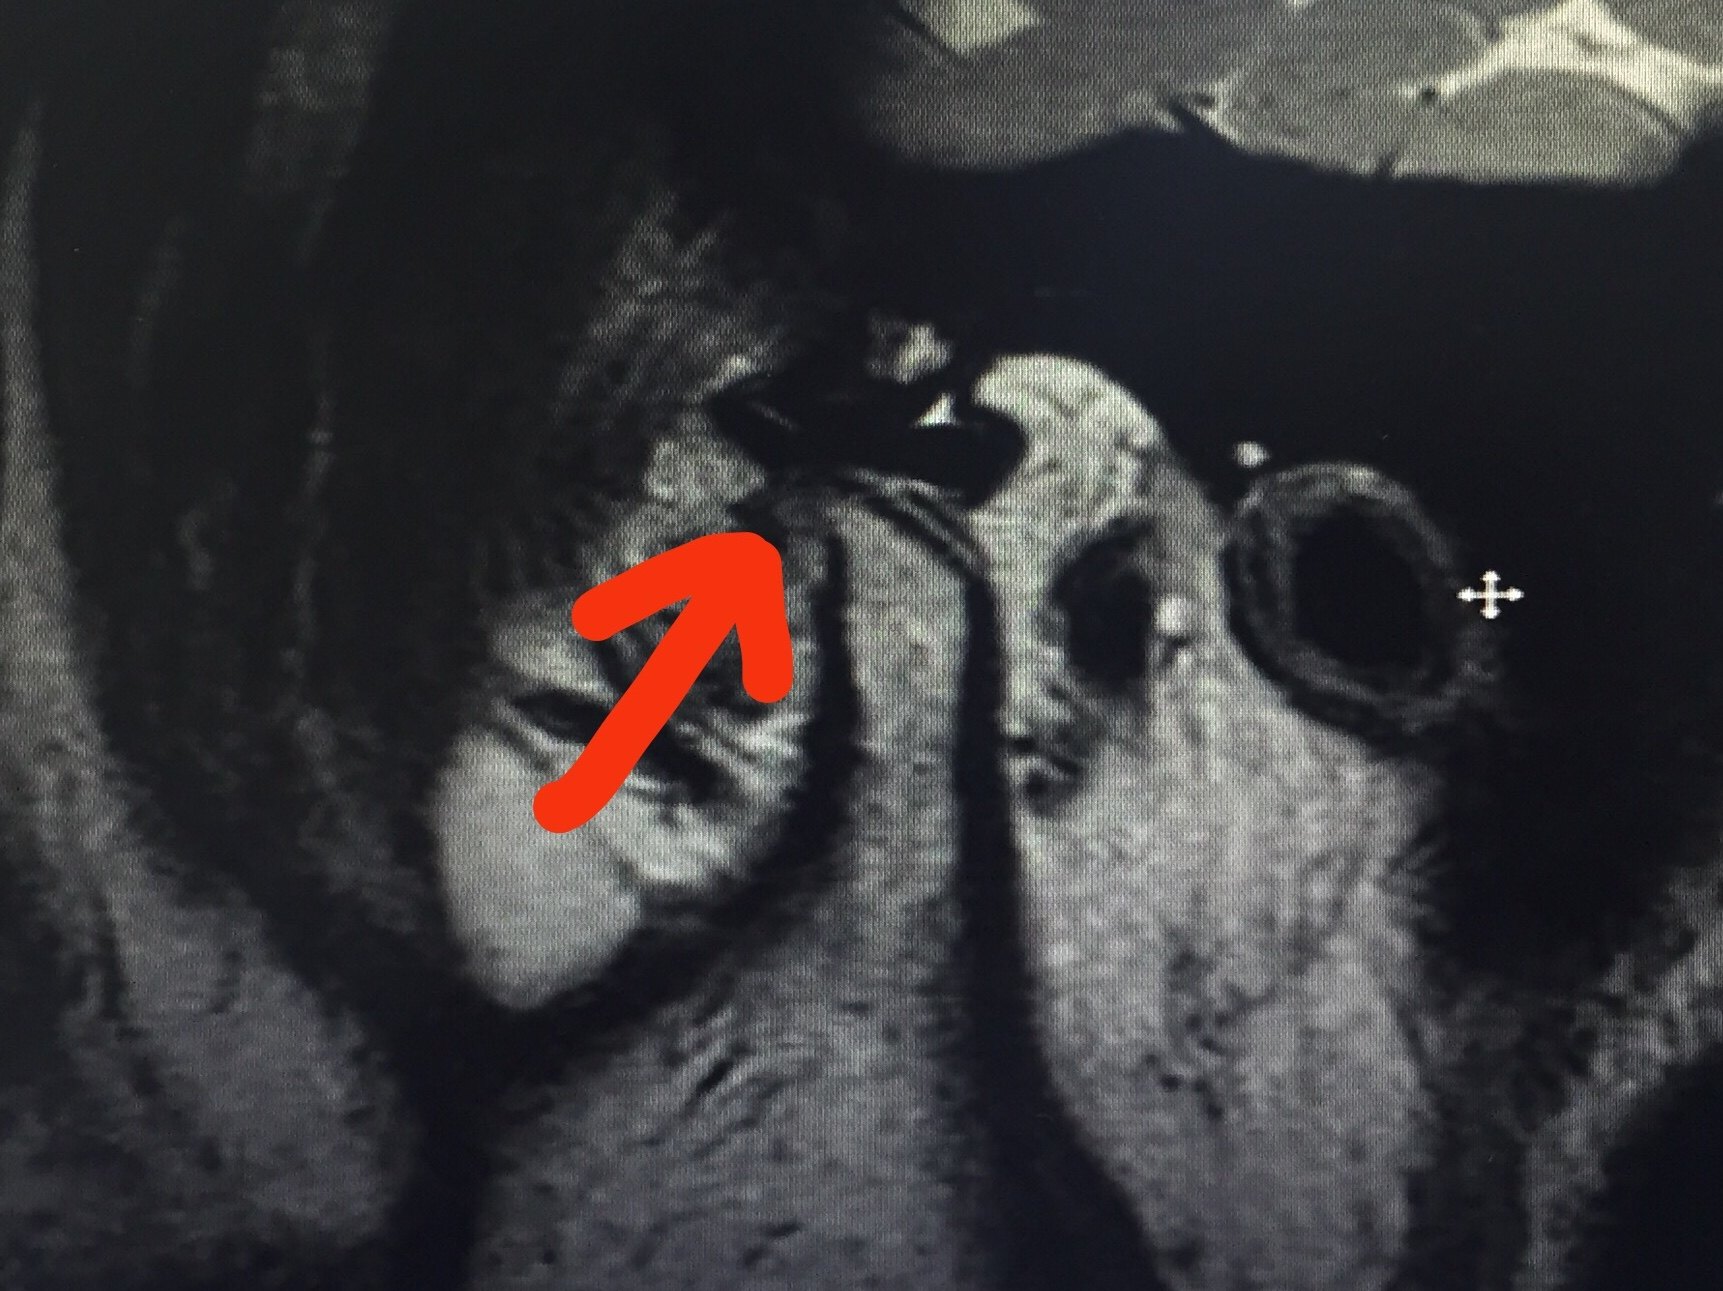

科普答疑不可复关节盘移位到底是什么

图片尺寸1440x1919

图片尺寸504x391